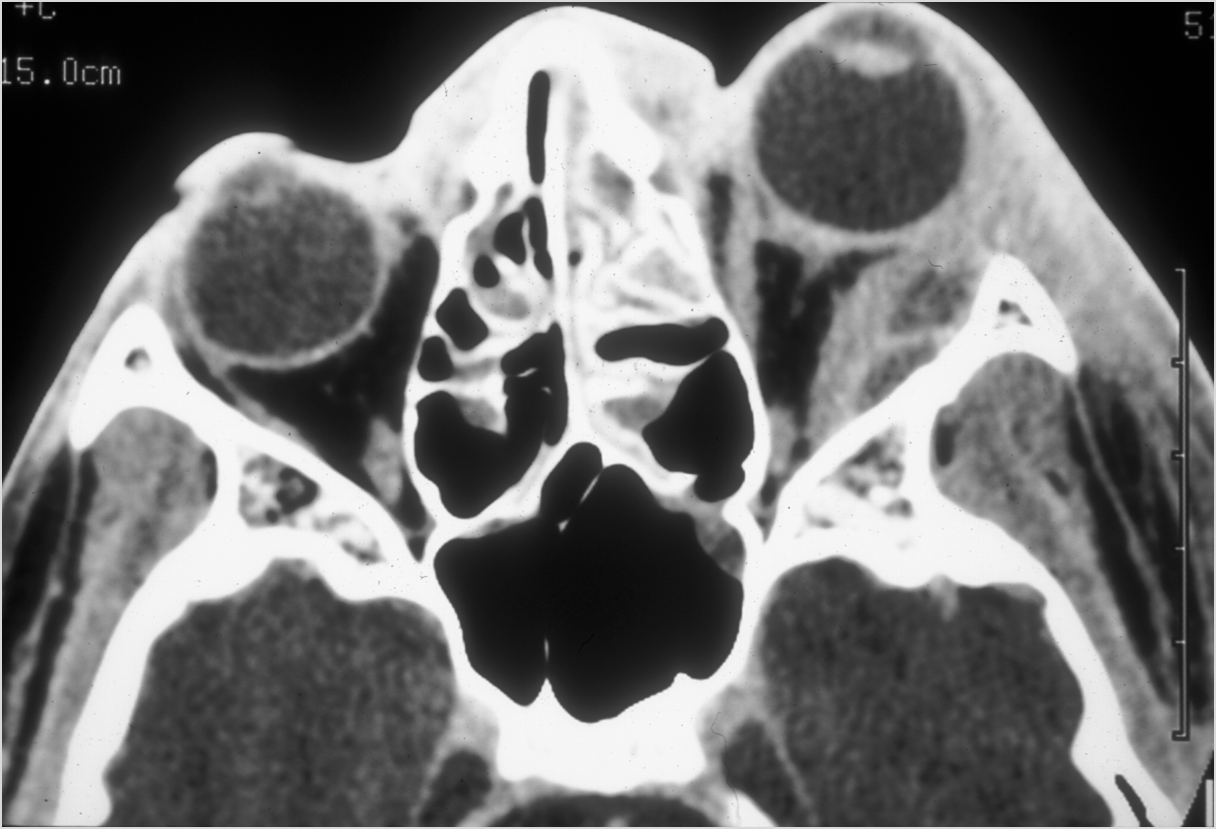

Eyes

Proptosis is present. [Yes/No]

The optic nerve is stretched in appearance. [Yes/No]

The posterior aspect of the globe is tented in appearance. [Yes/No]

The uveal scleral margin of the globe is swollen or enhancing abnormally. [Yes/No]

Signs of tension orbit or endophthalmitis are present. [Yes/No]